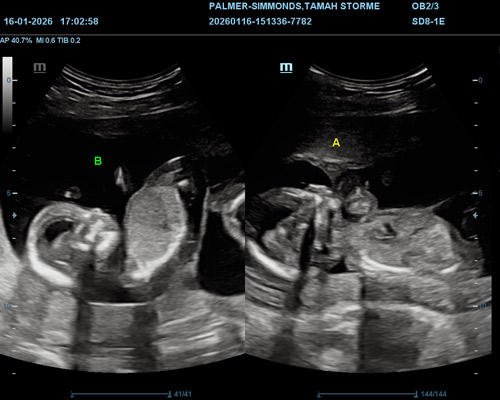

A twin gender scan is a detailed ultrasound designed to identify the gender of both babies as accurately as possible.

Because twins can move frequently and change position, extra care is taken during the scan to ensure each baby is clearly assessed. The sonographer will carefully observe both babies individually and explain what is visible throughout the appointment.

Our Scans